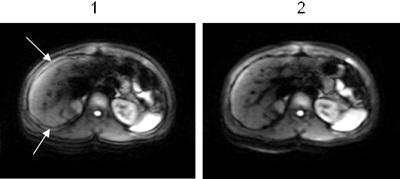

Figure 2. DW-EPI liver image comparison with Diffusion direction = All

Table 1. Image legend

NumberDescription

1Image acquired with Real Time Field Adjustment option turned Off.

The arrows indicate the area of misregistration.

2Image acquired with Real Time Field Adjustment option turned On.